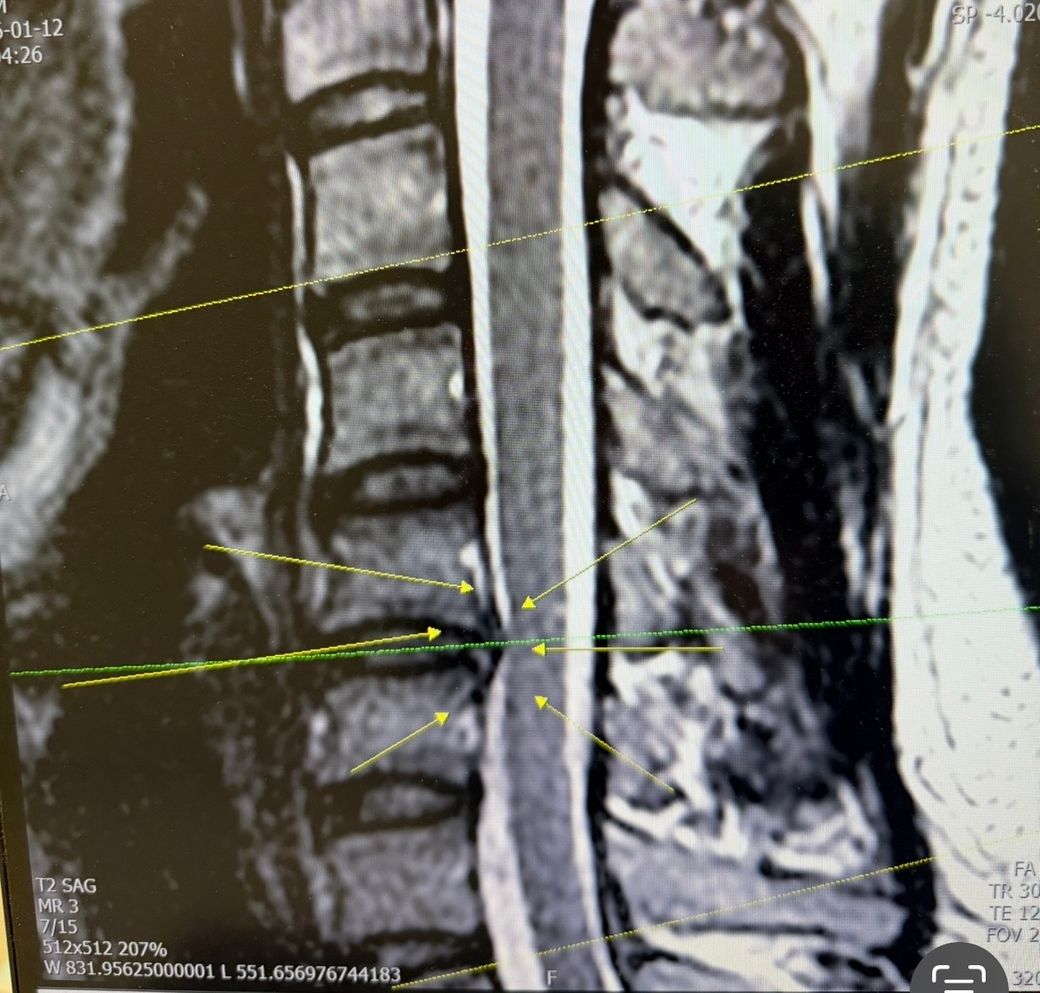

목 mri를 찍게 된 이유는 한때 오른쪽 목이 엄청 뻐근하고 어깨랑 팔까지 방사되어 찍게 되었는데 목디스크 판정을 받았고 신경(?)이 눌리고 있다고 들었습니다

MRI에서 “신경이 눌린다”는 표현은 대개 디스크 돌출이나 협착이 신경근을 접촉하거나 압박하는 상태를 의미합니다. 통증과 팔 방사통이 현재 거의 없다면 급박한 신경 손상 가능성은 높지 않은 경우가 많지만, 영상상 척수 압박이나 신호 변화가 있다면 이야기가 달라집니다. 이 부분은 실제 MRI 이미지를 직접 봐야만 심각도 판단이 가능합니다.

2. 사진을 통해서 보았을 때에는 디스크의 정도가 많이 심해 보이지는 않습니다. 그렇지만 영상 소견과 실질적으로 임상 증상의 정도가 일치하지 않을 수 있기 때문에 실질적으로 어느 정도다 하고 당장 평가를 내리기는 어렵습니다. 병원에 다시 가서 확실하게 평가를 받아보시는 것이 좋겠습니다. 당장 응급한 상태는 아니겠습니다.